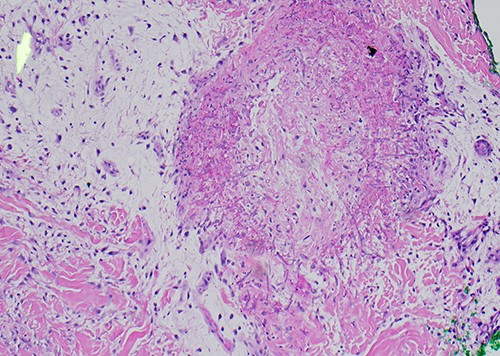

A 58-year-old male with a history of hypertension, hyperlipidemia, asthma, and newly diagnosed Hepatitis C presented with leukocytosis consistent with chronic myelogenous leukemia in blast crisis. He was given hydroxyurea and started on induction 7 + 3 idarubicin and cytarabine chemotherapy. The patient then developed neutropenic fever with multidrug-resistant Escherichia coli bacteremia and VRE enterococcus faecium. After 5 days of neutropenic fever, he developed a ‘knot’ on his left leg (Fig. 1). Physical exam revealed a nontender 1.5 cm violaceous firm indurated papule 2 cm above the left patella without evidence of cellulitis or infection. A total of 2 days later, the patient developed smaller satellite lesions on the left dorsal hand and chest. Dermatology was consulted and performed two 4 mm punch biopsies of the left patellar lesion for tissue staining and culture. Hematoxylin and eosin (H&E) staining revealed an obliterated blood vessel in the deep reticular dermis and numerous hyphae with septation and acute angle branching within the vessel wall consistent with angioinvasive fungus most consistent with angioinvasive aspergillosis (Figs 2 and 3). Biopsy of the wrist and further tissue cultures of the knee did not show any organisms but had reactive changes. Additionally, a chest computed tomography revealed new pulmonary nodules and atypical pneumonia with concern for disseminated disease. He was started on liposomal amphotericin and empiric voriconazole. At this time, urgent local excision of the knee was recommended for source control. A 4 × 5 cm lesion above the knee was excised with biopsy-proven clear margins and dressed with packing and a wound vaccum assisted closure (vac), as the lesion was proximal to a joint (Fig. 4). One month later, the patient received a split thickness skin graft. The patient tolerated surgical intervention well and had re-epithelialization of the donor site. He received three months of voriconazole for angioinvasive aspergillosis. One year later, there has been no recurrence or persistence of angioinvasive soft tissue or lung infection.

Original biopsy with numerous fungal hyphae demonstrating angioinvasion (H&E).